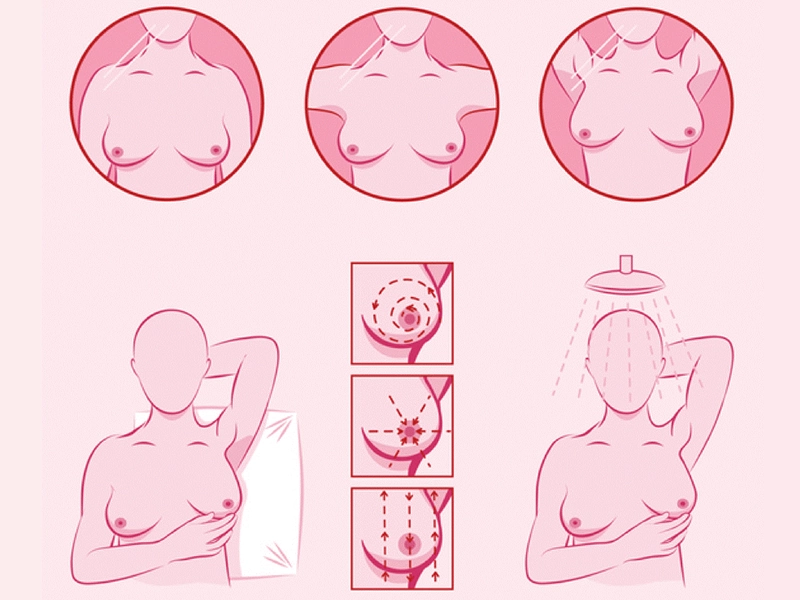

خودآزمایی پستان یکی از روشهای مهم و کم هزینه برای پایش سلامت سینههاست که هر زن میتواند به تنهایی و